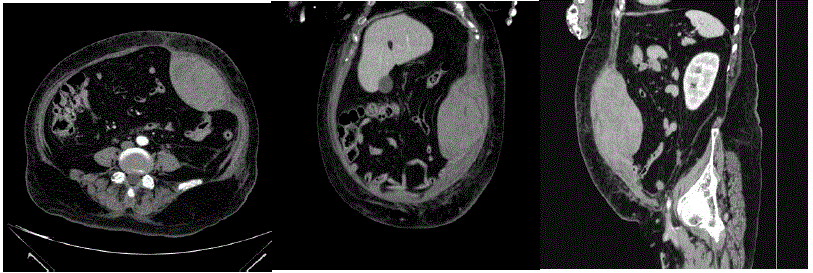

Realizada tomografia de abdome (imagem a seguir):